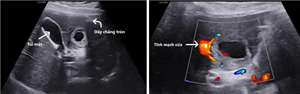

Tăng sinh mạch máu cơ tử cung - thông nối động tĩnh mạch mắc phải